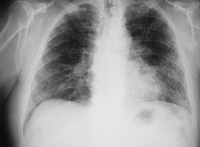

RT de enfermedad crónica por berilio

De la colección personal de Kenneth D. Rosenman, Michigan State University